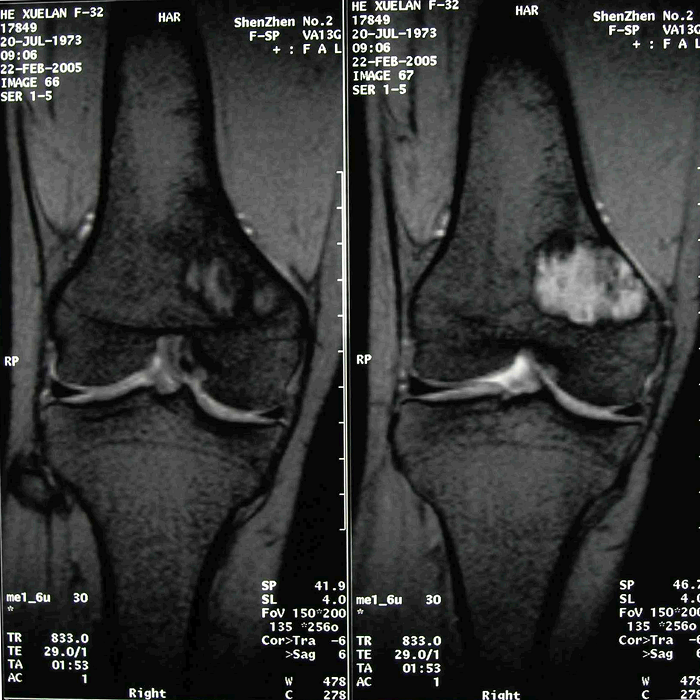

患者 女 28岁 右股骨远端良性纤维组织细胞瘤

图 2、3、4 术前MRI

2.MRI特点

病灶边界清楚,T1加权相呈等、高信号,T2加权相呈等信号,增强扫描时强化明显。